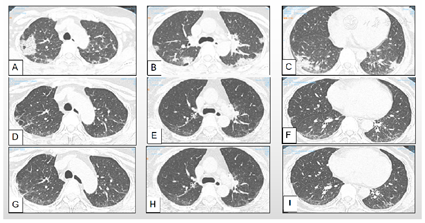

心电图为窦性心动过缓;骨密度检查低骨量;彩色超声:甲状腺弥漫性回声改变,双侧甲状旁腺区未见明显异常,二尖瓣、三尖瓣轻度反流(Ti:26 mmHg),左室舒张功能下降;肝实质弥漫性回声改变,右肾囊肿;支气管镜检查:左侧、右侧主支气管发现各叶段支气管内少量分泌物,各叶段支气管管口通畅,黏膜充血水肿。留置标本送检,ROSE未见菌丝;2019年8月9日检查肺部高分辨率(high resolution CT,HRCT)示⑴双肺间质性肺炎,建议治疗后复查;⑵双侧胸膜局限性增厚;⑶纵隔内及双侧腋下多发稍大淋巴结(图1A~C);肺功能检查:中度限制性通气功能障碍,肺弥散功能中度减退,小气道受累。

患者从2019年8月9日应用哌拉西林他唑巴坦钠4.5 g每8小时1次,共10 d,注射人免疫球蛋白20 g/d,共5 d,同时应用"贝前列腺素片40 µg每日3次","泼尼松30 mg每日1次(逐渐减量)","吡非尼酮0.3 g每日1次",应用奥美拉唑、钙片、阿法骨化醇等药物对症治疗;2019年8月24日开始每月静脉注射环磷酰胺1.0 g用6次,每3个月1.0 g用3次,累计9 g;后因为患者输注环磷酰胺后间质性肺炎较前加重(图2A~C),由于患者胃肠道副作用、月经周期紊乱、皮肤硬化缓解不明显、输液困难等原因,于2020年11月开始停用环磷酰胺输注,调整为口服托法替布5 mg每日2次,余治疗同前。

2021年9月复查,患者mRSS评分为13,血沉10.2 mm/h,C反应蛋白4.31 mg/dl,白细胞8.78×109/L,6MWD(6分钟步行试验) 512 m。患者间质性肺炎较前好转,肺纤维化评分Sverzellati视觉评分8分(2019年8月,2020年2月,2020年6月,2020年11月,2021年9月:23分→15分→8分→13分→8分)。

SSc来源于希腊语中的硬和皮肤两个词语。虽然SSc被认为是一种所谓的孤儿病,患病率低,但它导致不同比例的发病率和病死率,由于初始症状无特异性,一般临床医师在检查和治疗方面缺乏经验,而诊断延误又会加剧这种病情;临床中相当比例的SSc-ILD患者无症状,特别是在疾病的初始阶段以及行动受到限制时,患者又无肺内表现,HRCT作为重要的检查方法已被证明具有良好的诊断精度。本文通过总结对患者的诊断及并发症ILD的筛查,并针对指端溃疡、皮肤和肺纤维化给予积极治疗,密切随诊患者病情变化,在患者间质性肺炎程度加重时积极寻找病因并及时调整治疗方案。该患者在诊断早期通过HRCT及时发现ILD,并给予针对性治疗。